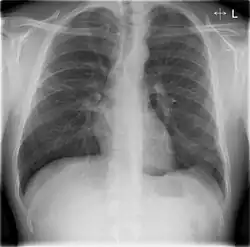

Chest X-rays and X-ray computed tomography (CT) can reveal areas of opacity (seen as white), indicating consolidation.[14] CAP does not always appear on x-rays, sometimes because the disease is in its initial stages or involves a part of the lung not clearly visible on x-ray. In some cases, chest CT can reveal pneumonia not seen on x-rays. However, congestive heart failure or other types of lung damage can mimic CAP on x-ray.[16]

When signs of pneumonia are discovered during evaluation, chest X-rays and examination of the blood and sputum for infectious microorganisms may be done to support a diagnosis of CAP. The diagnostic tools employed will depend on the severity of illness, local practices and concern about complications of the infection. All patients with CAP should have their blood oxygen monitored with pulse oximetry. In some cases, arterial blood gas analysis may be required to determine the amount of oxygen in the blood. A complete blood count (CBC) may reveal extra white blood cells, indicating infection.

The CAP outpatient mortality rate is less than one percent, with fever typically responding within the first two days of therapy, and other symptoms abating in the first week. However, X-rays may remain abnormal for at least a month. Hospitalized patients have an average mortality rate of 12 percent, with the rate rising to 40 percent for patients with bloodstream infections or those who require intensive care.[30] Factors increasing mortality are identical to those indicating hospitalization.

When CAP does not respond to treatment, this may indicate a previously unknown health problem, a treatment complication, inappropriate antibiotics for the causative organism, a previously unsuspected microorganism (such as tuberculosis) or a condition mimicking CAP (such as granuloma with polyangiitis). Additional tests include X-ray computed tomography, bronchoscopy or lung biopsy.